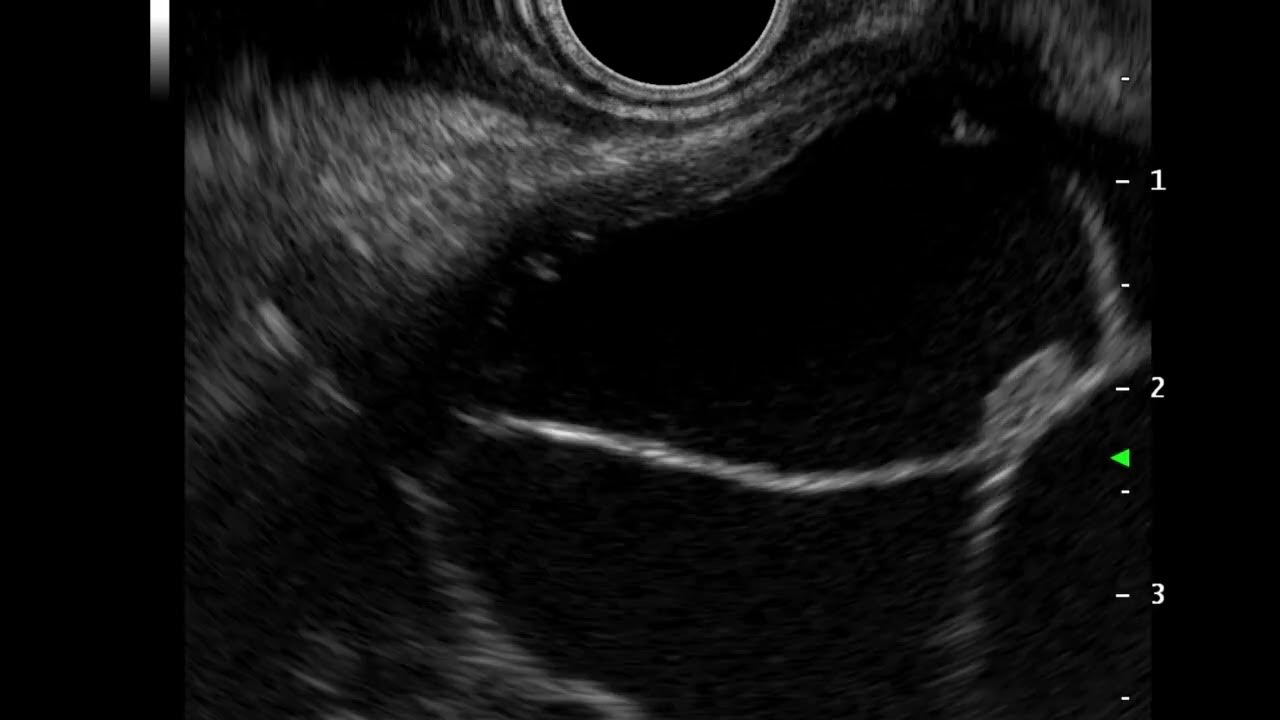

The spearfishing sign differentiating mucin from mural nodules in

The spearfishing sign differentiating mucin from mural nodules in What Is A Mural Nodule In Pancreas Pancreatitis, cysts that are larger than 3 cm in diameter, an. — high risk features include obstructive jaundice, an enhancing mural nodule and a main pancreatic duct 1 centimeter or larger. — the presence of an enhancing mural nodule ≥5 mm has been used as a positive predictor of advanced pancreatic neoplasia in ipmn;. — a solid. What Is A Mural Nodule In Pancreas.